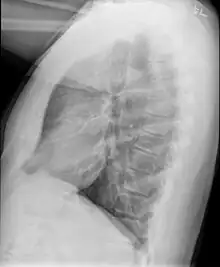

-

Chest radiograph demonstrates thickening and dilatation of the bronchioles